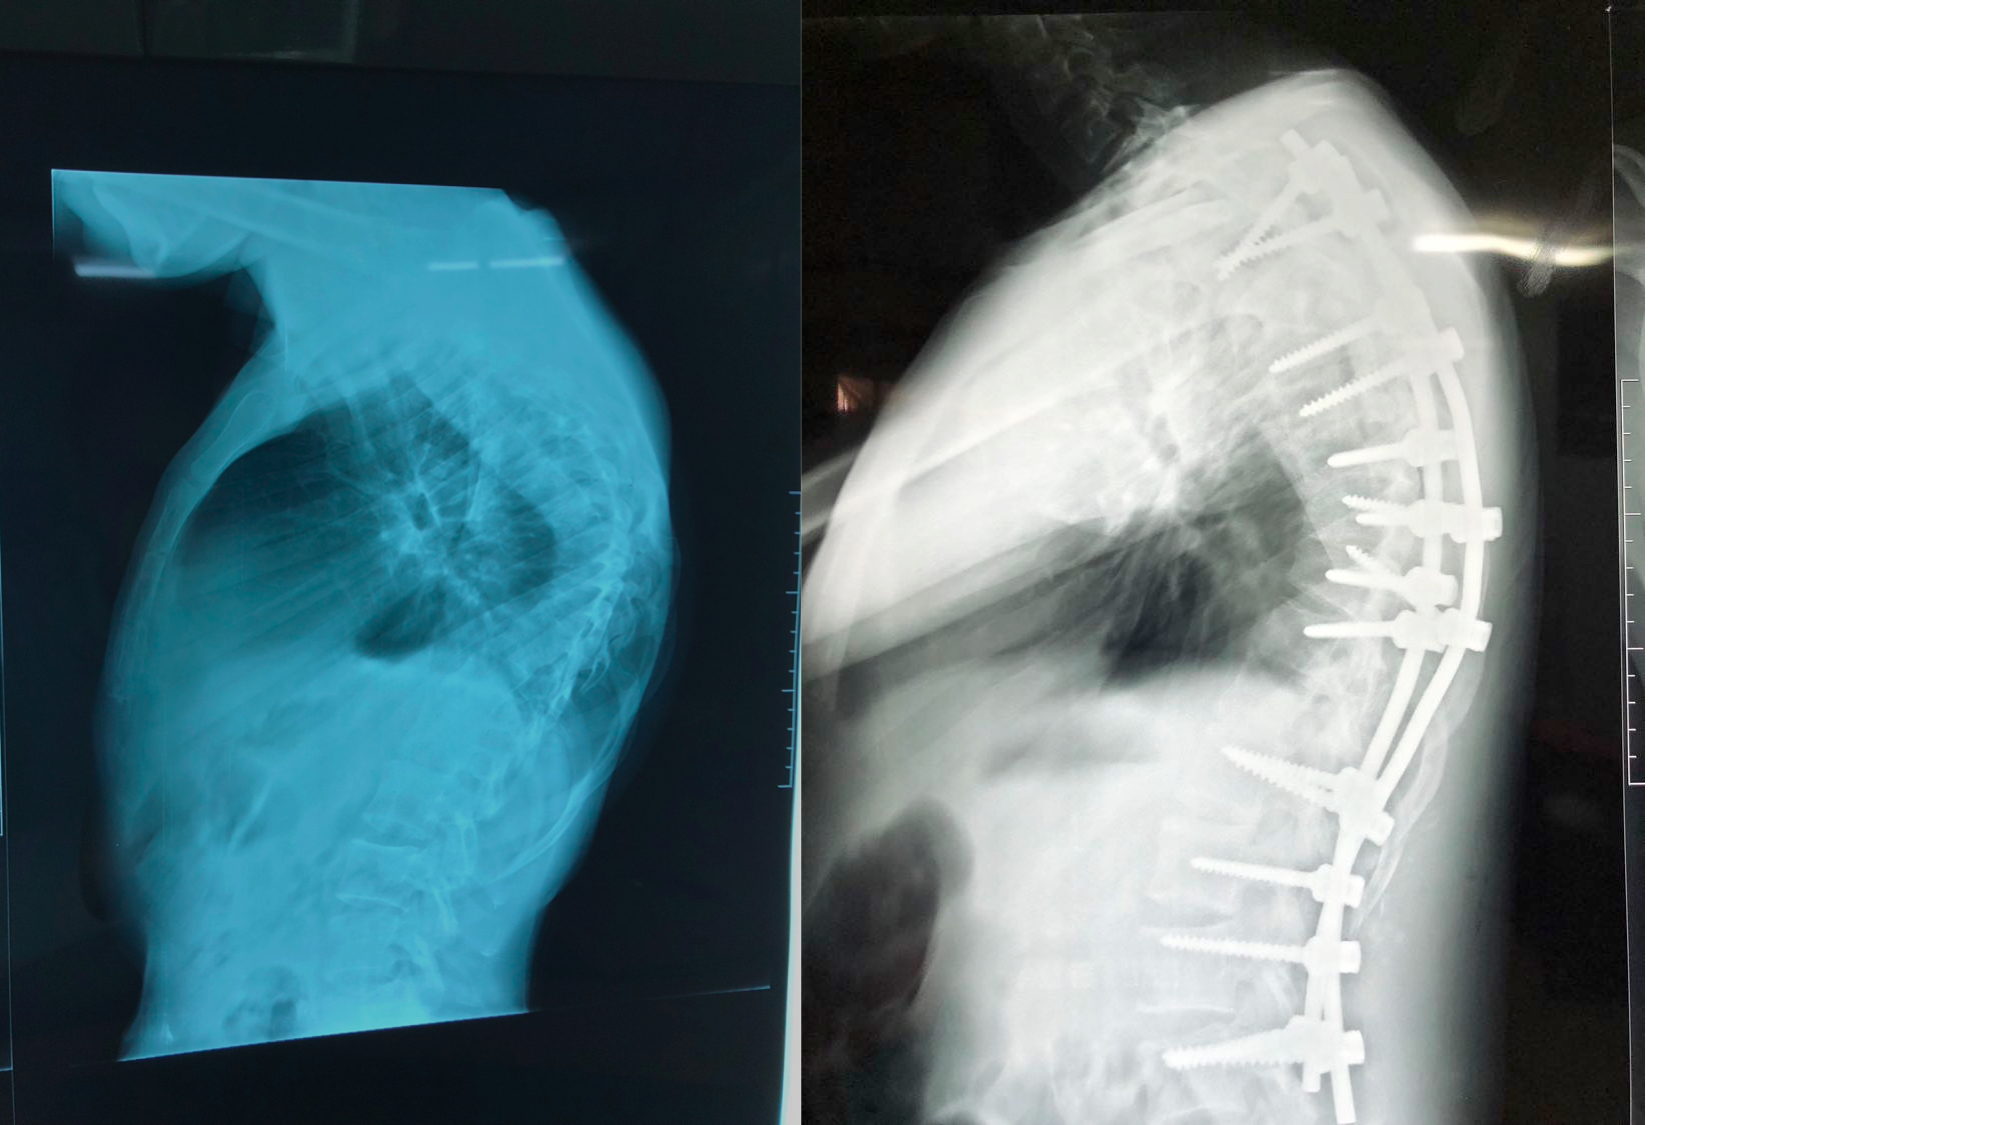

I was also able to meet the first two spine surgery fellows at AaBET. They are both neurosurgeons. The plan after next year is to alternate orthopedic with neurosurgery spine fellows. In addition to their teaching at AaBET, they are mentored by Dr Fasil Mesfin of Univeristy of Missouri, with whom they have weekly cases conferences. They were excited to show me two massive spine tumors they just operated on, one a giant, dumbbell shaped neurofibroma of the lower thoracic spine with bone involvement and preoperative paraparesis; the other a huge aneurysmal bone cyst of posterior lumbar element. Both needed pedicle screw instrumentation and big exposures. I am not a spine surgeon but the operative photos and postop xrays were very impressive.